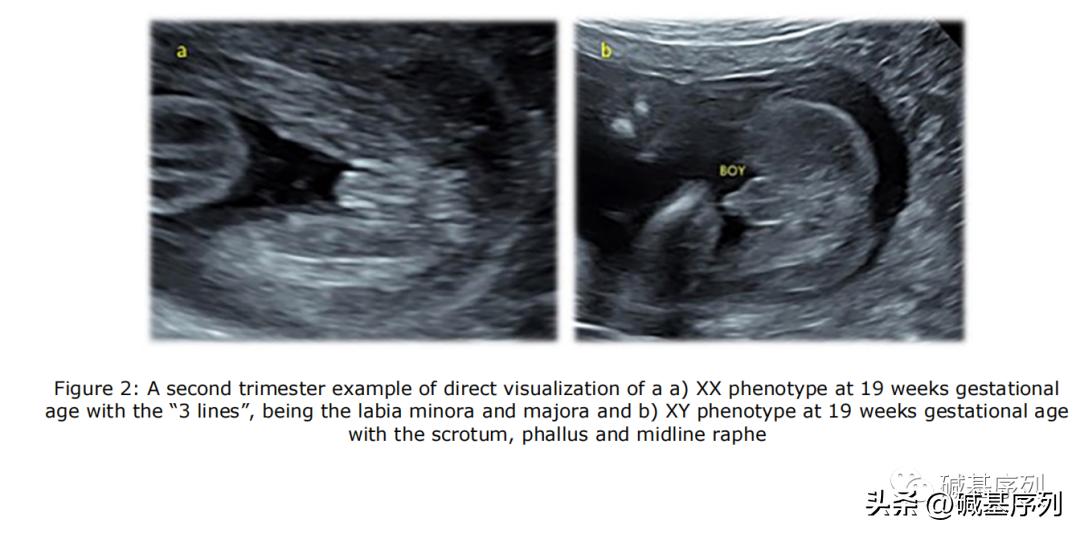

XX和XY基因型胎儿的超声表现

产前无创筛查(non-invasive prenatal testing, NIPT)发现性染色体异常。NIPT对性染色体非整倍体的阳性预测值(positive predictive value, PPV)约为32% ~ 57.6%。

在 Richardson等(2017) 研究中,NIPT提示的胎儿性别与孕期B超显示的胎儿性别之间不一致性的发生率为 1/1845 ,这个发生率已经 相当于或大于 一些常见的胎儿非整倍体或基因组疾病的发生率。例如,2q11.2缺失综合征(22q11.2 deletion syndrome, 22q11.2DS)是人类最常见的基因组疾病,活产儿发病率约 1/4 000~6 000。微缺失/微重复综合征发病率为1/200 000~1/4000,合并发病率近1/600。